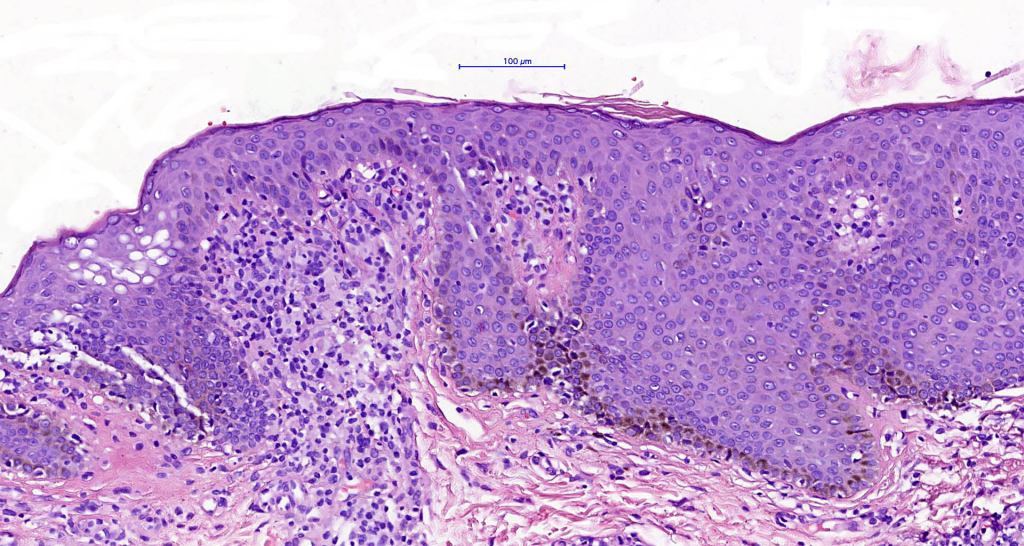

Histological features

•Variable histological features ranging from a non-specific superficial perivascular or band-like dermal infiltrate with minimal or no epidermotropism through to mycosis fungoides-like histology; can mimic atopic dermatitis

•Sézary cells are CD45RO, CLA, CD158 & CD4+

.Loss of CD7 (40% or more) & CD26 (30% or more)